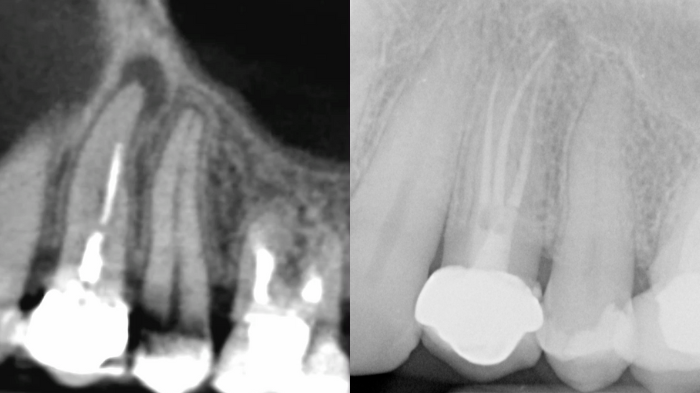

Necrosis pulpar en diente 45 con bifurcación en el tercio medio del conducto Caso clínico del doctor Francisco…